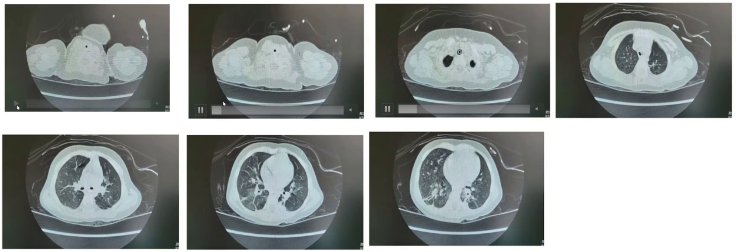

(3)影像学检查

4.15胸部CT:两肺有渗出、部分实变及局灶性肺气肿。